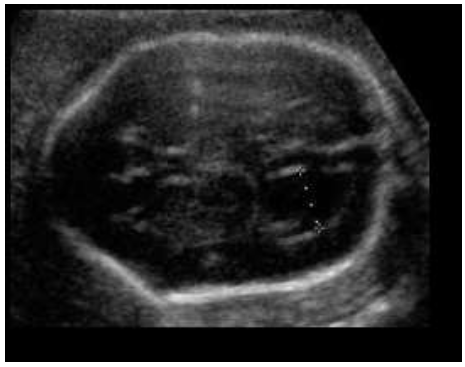

O mioma (leiomioma) uterino é um tumor benigno, muito comum, que pode acometer até 70% das mulheres com 50 anos de idade. Para sistematizar a descrição dos miomas, foi criada a classificação da FIGO (Federação Internacional de Ginecologia e Obstetrícia) juntamente com o grupo MUSA (Morphological Uterus Sonografic Assessment), utilizando estes parâmetros classifique o nódulo abaixo:

Enunciado 3377073-1